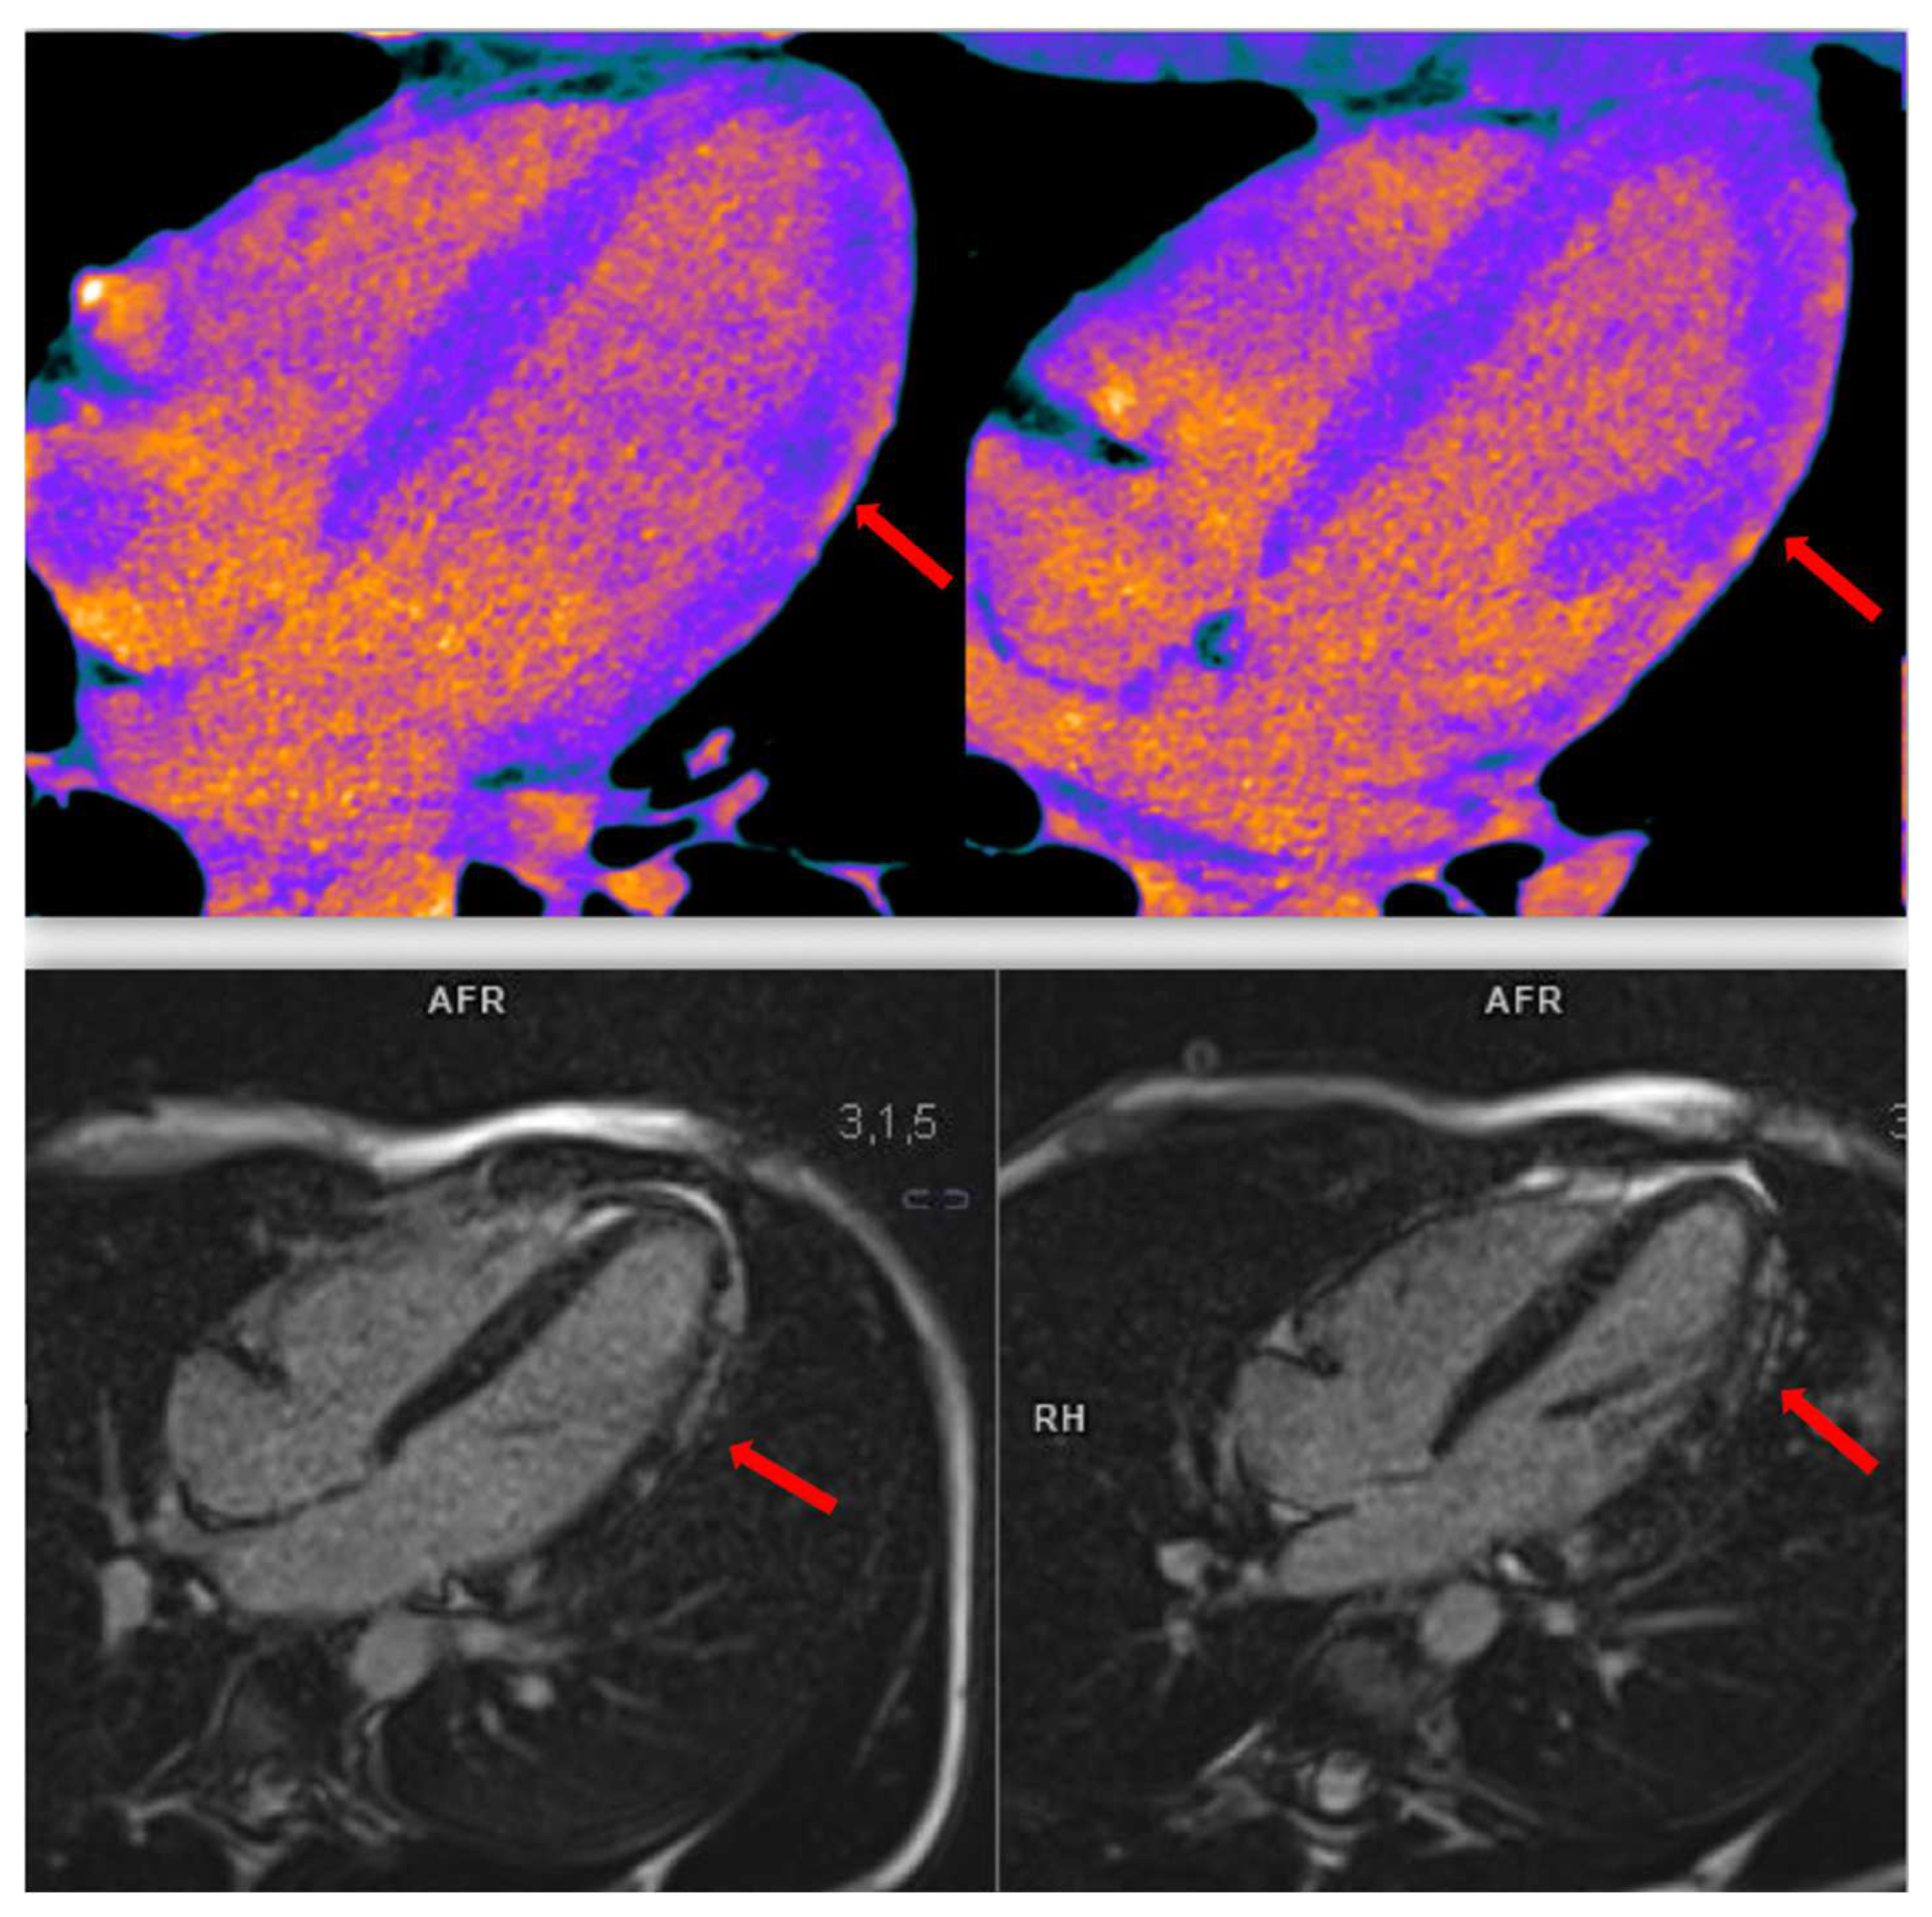

- Eitel, I.; Friedrich, M.G. T2-Weighted Cardiovascular Magnetic Resonance in Acute Cardiac Disease. J. Cardiovasc. Magn. Reson. 2011, 13, 13. [Google Scholar] [CrossRef] [PubMed]

- Scally, C.; Rudd, A.; Mezincescu, A.; Wilson, H.; Srivanasan, J.; Horgan, G.; Broadhurst, P.; Newby, D.E.; Henning, A.; Dawson, D.K. Persistent Long-Term Structural, Functional, and Metabolic Changes After Stress-Induced (Takotsubo) Cardiomyopathy. Circulation 2018, 137, 1039–1048. [Google Scholar] [CrossRef]

- Arcari, L.; Camastra, G.; Ciolina, F.; Limite, L.R.; Danti, M.; Sclafani, M.; Ansalone, G.; Musumeci, M.B.; Nagel, E.; Puntmann, V.; et al. Myocardial Oedema Contributes to Interstitial Expansion and Associates with Mechanical and Electrocardiographic Changes in Takotsubo Syndrome: A CMR T1 and T2 Mapping Study. Eur. Heart J. Cardiovasc. Imaging 2023, 24, 1082–1091. [Google Scholar] [CrossRef]

- Ojha, V.; Khurana, R.; Ganga, K.P.; Kumar, S. Advanced Cardiac Magnetic Resonance Imaging inTakotsubo Cardiomyopathy. Br. J. Radiol. 2020, 93, 20200514. [Google Scholar] [CrossRef]